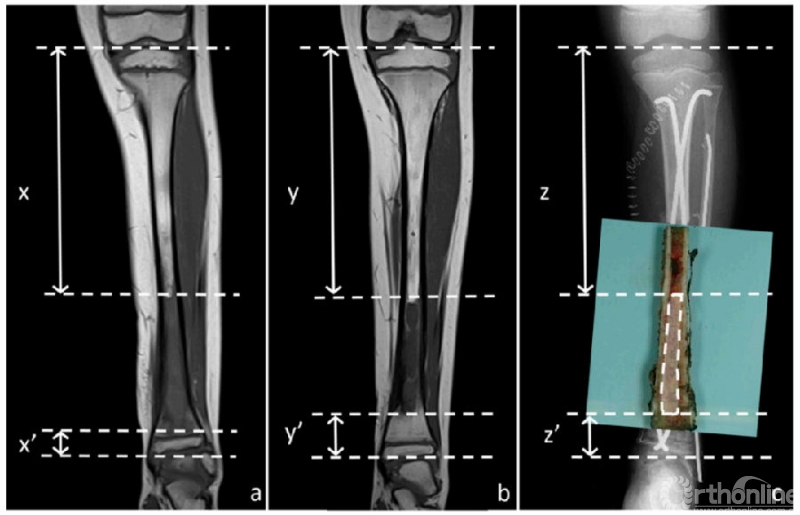

由放射科医生以标准化方式对化疗前、后的MRI进行分析。研究纳入了三个MRI序列:T1加权、T1增强以及STIR序列。对于每个序列,通过冠状面上的异常信号和正常信号来确定肿瘤的范围。测量骨内异常信号的近端和远端边界与相应的骨末端之间的距离(图1A和1B)。

图1 8岁男孩左胫骨尤文氏肉瘤。图1A,化疗前T1加权。表示骨近端到肿瘤近端界限的距离(x)和骨远端到肿瘤远端界限的距离(x’);图1B,化疗后T1加权。表示骨近端到肿瘤近端界限的距离(y)和骨远端到肿瘤远端界限的距离(y’);图1C,显示组织学测量。在本例中,近端(z)和远端(z’)测量值表示各自肿瘤极限与手术标本上切割的骨之间的距离,加上计算机X光片上测量的残骨长度。

在切除的标本上,测量了肿瘤边界(近端和远端)与相应骨末端之间的距离。当末端包括骨骺时,这种组织学测量就足够了。当末端是骨切面时,在组织学测量中添加了术后X线检查中测量的骨切面与残余骨末端之间的距离。这2个距离的总和对应于肿瘤相对于骨末端的距离(图1C)。

12例化疗前MRI显示骨骺信号异常,其中8例化疗后MRI仍显示异常信号。然而病理学评估显示,8例中只有2例肿瘤发生骨骺累及;其余6例未见骨骺异常。化疗后MRI显示骨骺信号异常的4例中,1例行骨骺保留切除,病理报告为R0切缘。根据化疗前MRI计划的手术切除是不可能保留骨骺的(图2)。在其他3例中,骨骺病理学完全正常。平均随访68个月,组织学边界阴性的患者局部未见复发。

图2 右股骨尤因肉瘤,3岁女童。图2A 化疗前T1加权,显示骨骺信号异常;图2B 化疗后T1加权,显示骨骺信号完全正常化;图2C 术后3年X线片,骨骺保存良好,边缘健康。